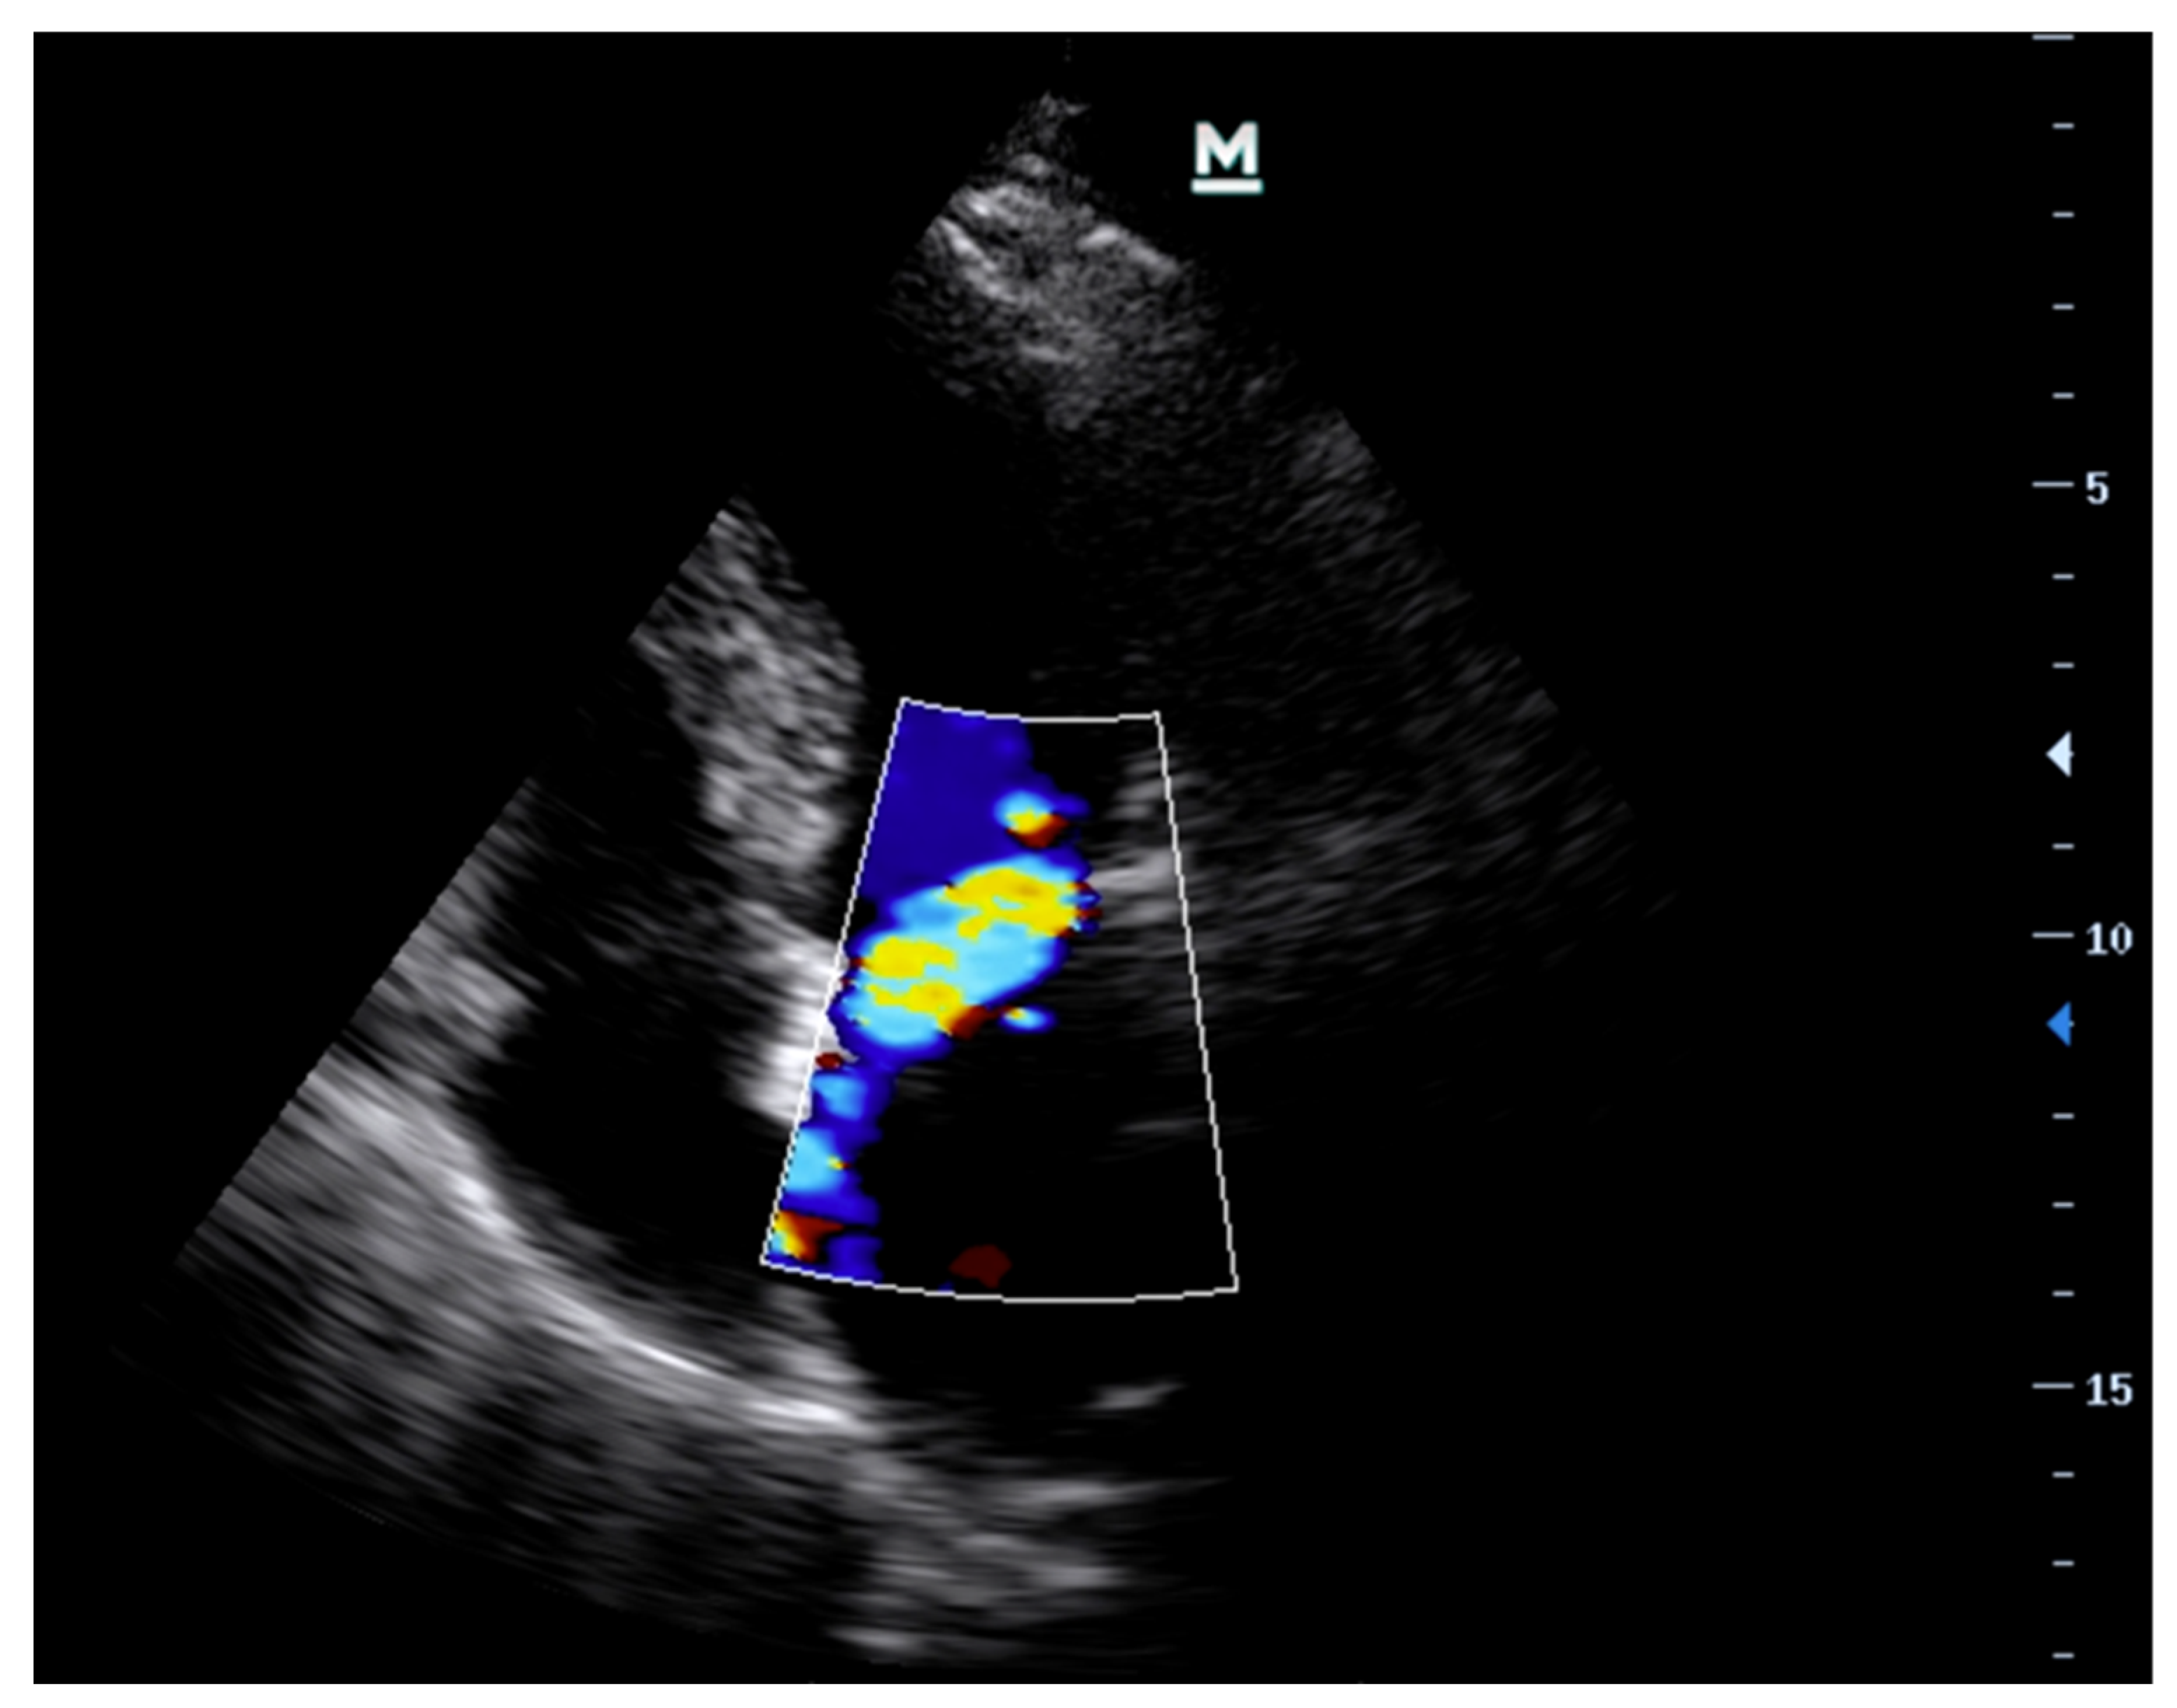

- Imaging ModesVarious ultrasound modalities are used to assess the structure and function of heart valves. Two-dimensional (2D) imaging is generally used for structural assessment, colour flow doppler (CFD) is used to evaluate blood flow across the valves, and continuous-wave (CWD) and pulsed-wave doppler (PWD) techniques are used to measure flow velocities and gradients across valves. Integrating these imaging modalities can offer a comprehensive assessment of valvular function and aid in identifying specific pathologies (Table 1) [27,38].

| Colour Flow Doppler (CFD) | Colour flow is not a good marker for assessment of severity of MR or AR. However, it may assist with determining aetiology—usually eccentric jets if prolapse/flail in the direction that is away from the prolapsing/flail leaflet i.e., anterior mitral valve leaflet prolapse leads to a posteriorly directed jet. | Central jet, typically directed towards the posterior wall of the left ventricle. |